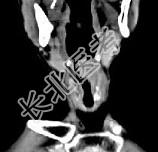

- 单项选择题男,53岁, 咽部不适半年余,近两个月感咽部疼痛, 声嘶,CT如图所示, 应诊断是 ( )

D、喉癌

E、梨状窝癌